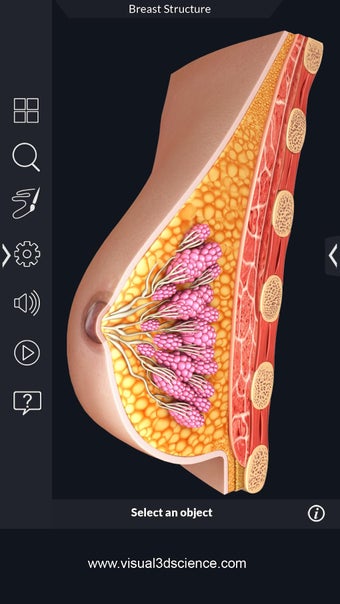

La anatomía humana es una aplicación educativa médica que te permite explorar el cuerpo humano desde todos los ángulos. Ofrece una mirada detallada a la anatomía de los diferentes sistemas, así como a los órganos y sus funciones. Es una referencia perfecta para estudiantes y profesores de medicina.

Puedes seleccionar cada parte del cuerpo por separado para ver su nombre o leer información relacionada. Puedes ocultar y mostrar cada parte del cuerpo, así como rotar 360° alrededor de un modelo 3D altamente realista. Puedes dibujar en la pantalla o compartir capturas de pantalla con tus amigos. Puedes encontrar la definición de cada parte del cuerpo y su anatomía.